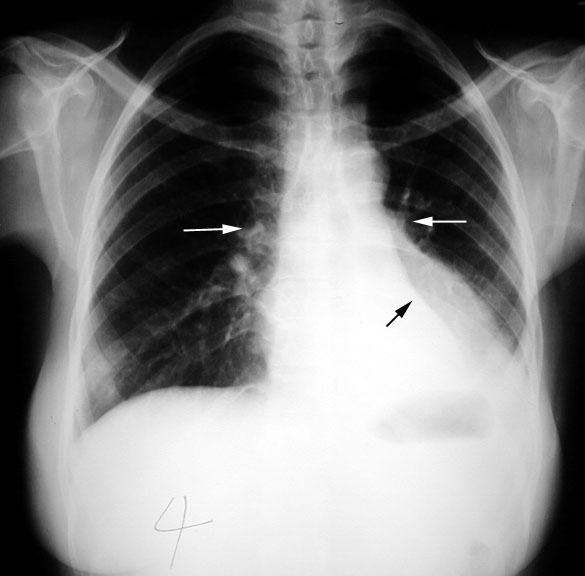

weekly clinical round for undergraduate from 8 to 11 AM during which interpretation of CHEST X rays was done for all cases of cardiothoracic surgery, gived by 2 staf member for 3 months